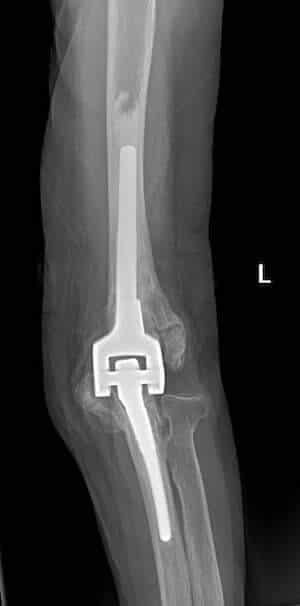

Η αρθροπλαστική αγκώνα είναι η χειρουργική επέμβαση που περιλαμβάνει την αντικατάσταση των φθαρμένων επιφανειών του αγκώνα με μεταλλικά εμφυτεύματα. Υπάρχουν 2 κύρια είδη αρθροπλαστικής αγκώνα: η ολική αρθροπλαστική αγκώνα (ΤΕΑ, ή total elbow arthroplasty) και η ημιαρθροπλαστική. Στην ολική αρθροπλαστική αντικαθίστανται και οι δύο αρθρικές επιφάνειες με μεταλλικές προθέσεις που αρθρώνονται μεταξύ τους. Χρησιμοποιείται κυρίως στην οστεοαρθρίτιδα που συνήθως προκαλεί την φθορά και των 2 αρθρικών επιφανειών. Στην ημιαρθροπλαστική (“hemi”), αντικαθίσταται με πρόθεση μόνο η μία από τις αρθρικές επιφάνειες αυτή του βραχιονίου. Η ημιαρθροπλαστική χρησιμοποιείται κυρίως σε πολύ περιφερικά κατάγματα του περιφερικού βραχιονίου, που δεν δύνανται να επιδιορθωθούν με εσωτερική οστεοσύνθεση.

Το χειρουργείο γίνεται σε πλάγια ή ύπτια θέση. Ο χειρουργός πραγματοποιεί μία τομή στο πίσω μέρος του αγκώνα και στη συνέχεια βρίσκει και προστατεύει το ωλένιο νεύρο. Οι φθαρμένες αρθρικές επιφάνειες κόβονται με ειδικούς οδηγούς και οι προθέσεις στερεώνονται με τη βοήθεια τσιμέντου, το οποίο σκληραίνει σε περίπου 10 λεπτά. Το τραύμα κλείνεται κατά στρώματα και εφαρμόζεται μία χαλαρή περίδεση. Το άκρο τοποθετείται σε μία ανάρτηση.